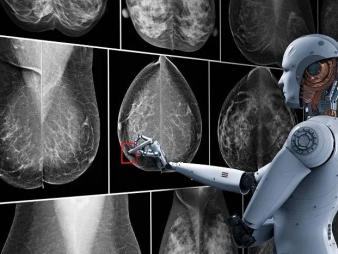

In unserem diagnostischen Zentrum in Lübeck steht das gesamte Spektrum der modernen Radiologie zur Verfügung, mit den neuesten Entwicklungen wie 3D-Bildgebung, Ganzkörper-MRT, MR-Mammographie und digitaler Mammographie einschließlich Zweitbefundung durch künstliche Intelligenz. Erfahren Sie hier, wie Sie sich anmelden können, wie Sie unser behindertengerechtes Zentrum erreichen und was Sie vor Untersuchungen zu beachten haben.